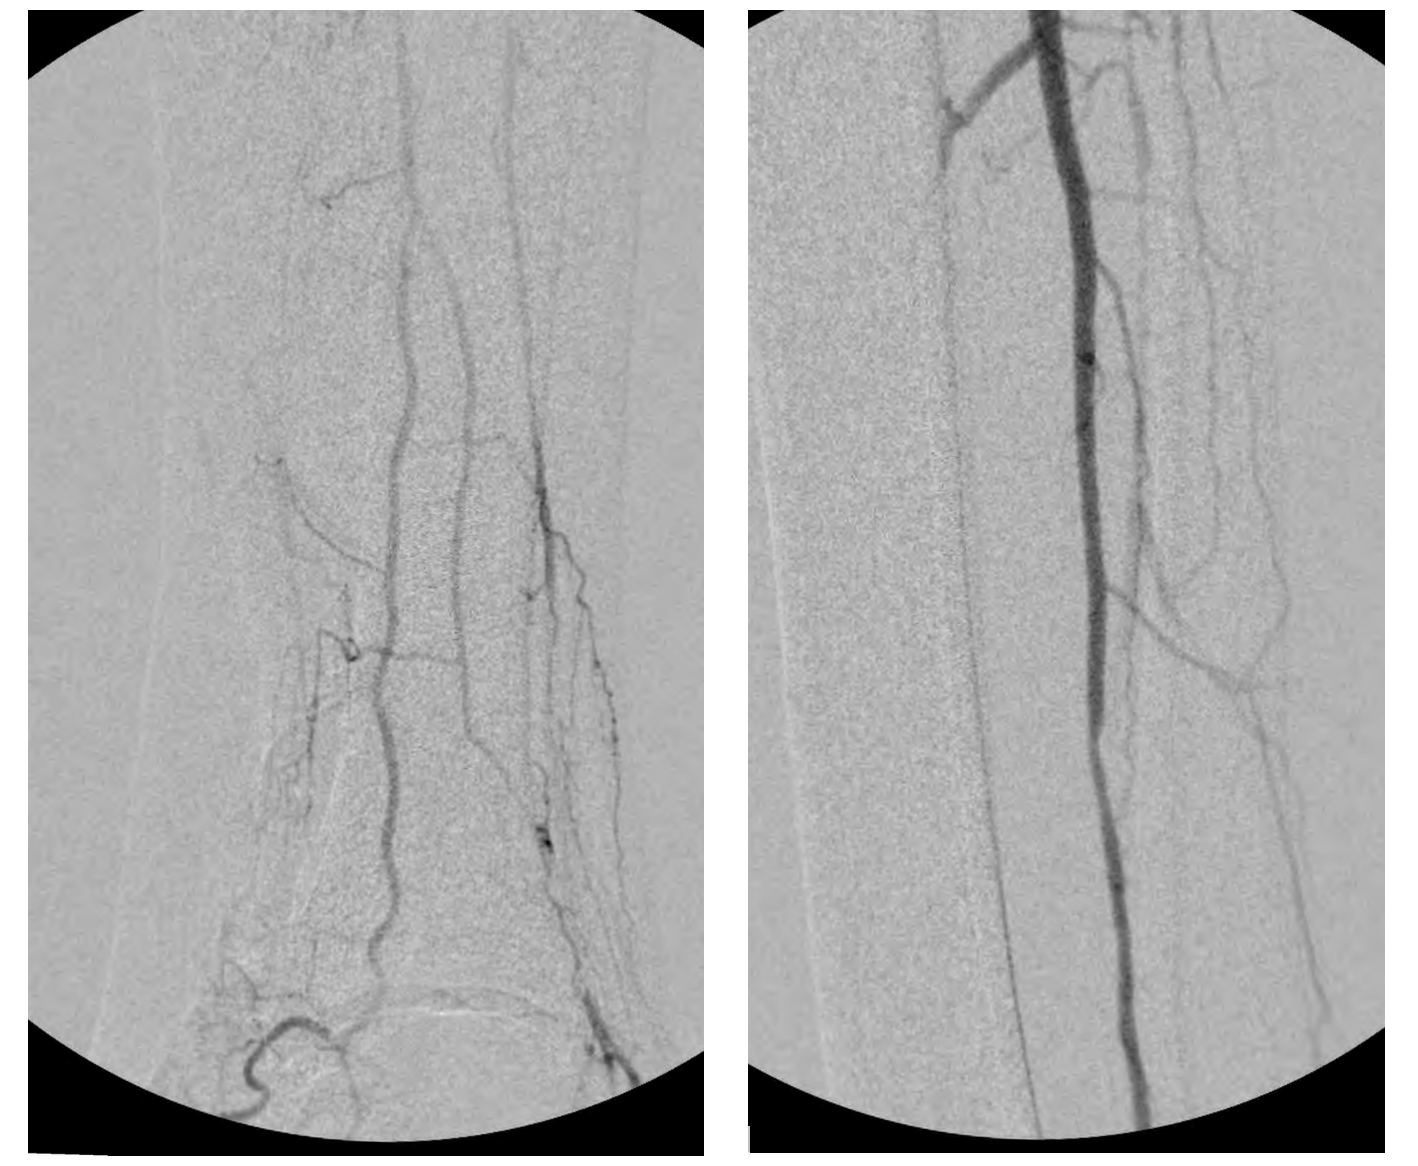

This allowed advancement of the antegrade wire (from the “up and over” access) across the occlusion in the far-distal anterior tibial artery into the dorsalis pedis artery. This was achieved carefully under extravascular ultrasound visualization. Next, completion angioplasty was performed with a 3-mm angioplasty balloon across the entirety of the distal anterior tibial artery occlusion into the patent dorsalis pedis artery (Figure 10).

The anterior tibial artery was successfully recanalized, with robust flow established into the dorsalis pedis artery (Figures 11 and 12). The patient tolerated the procedure well and did not have any complications. At 4 weeks post-intervention, the patient’s ulcer had significantly reduced in size/depth and was almost healed.